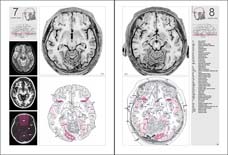

Atlas of the HUMAN BRAIN

Example pages from the printed book:

atlases. The new edition is completely redesigned, with additional magnetic

resonance images, line drawings, and an extensively expanded section of coronal

images. The number of hemisphere sections has been doubled, and all planes of

sections are placed within the Talairach space. The

format of the atlas has been enlarged and the information reorganized on the